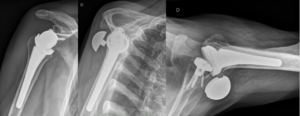

Reverse shoulder arthroplasty is a more reliable treatment than hemiarthroplasty for complex proximal humerus fractures at least in elderly patients because its functional outcomes appear to depend less on tuberosity healing and rotator cuff integrity (Figure).[90]

Reverse shoulder athroplasty for fracture. Frontal, axial and lateral Lamy radiographs after a reverse total shoulder implant. Note the lower positioning of the glenoid baseplate, the satisfactory reconstruction of the tuberosities, and the absence of cement at the autograft level.

Reverse shoulder arthroplasty for malunion of proximal humeral fracture. A) Anteroposterior radiograph of a malunited proximal humerus fracture; B) post-operative radiograph of the fracture sequelae treated with reverse shoulder arthroplasty.

Locked dislocation of a right shoulder. On the right, postoperative X-ray.

Revision surgery after primary shoulder arthroplasty (i.e. hemiarthroplasty, resurfacing or total shoulder arthroplasty) produced high patient satisfaction (Figure). It is, however, associated with higher complication and failure rates compared to reverse shoulder arthroplasty for patients without previous arthroplasty.[93]

A) Anteroposterior radiograph of a failed anatomic total shoulder arthroplasty; B) Anteroposterior post-operative radiograph after reverse shoulder arthroplasty.